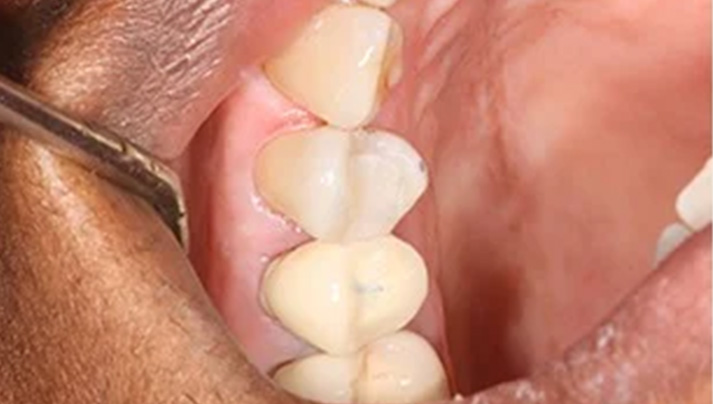

Before and Afters – White Fillings